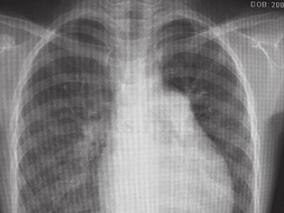

1小时条评论患者,男,17岁。自2006年来逐渐出现活动耐力下降,上楼时易气短,此次因活动后气短、乏力1年,晕厥2次来医院就诊,经过一系列检查被诊断为慢性血栓栓塞性肺动脉高压。然而,该患者年轻且无外伤、手术、卧床等血栓形成的易患因素,是什么原因导致患者形成血栓呢? ...

1小时条评论患者,男,17岁。自2006年来逐渐出现活动耐力下降,上楼时易气短,此次因“活动后气短、乏力1年,晕厥2次”来医院就诊,经过一系列检查被诊断为“慢性血栓栓塞性肺动脉高压”。然而,该患者年轻且无外伤、手术、卧床等血栓形成的易患因素,是什么原因导致患者形成血...